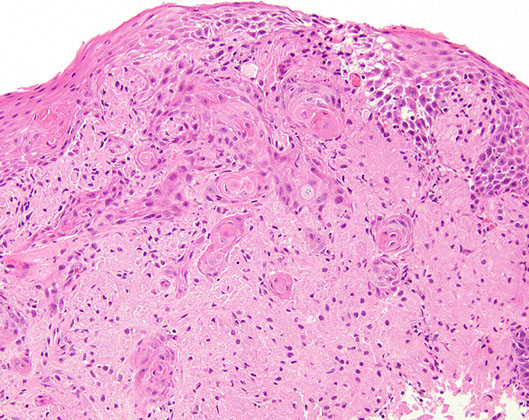

Can have pseudoepitheliomatous hyperplasia on top of them which can look like SCC!!

- can tell the difference bc pseudoepitheliomatous hyperplasia will still have bridging between the cells

Granular cell tumor with striking pseudoepitheliomatous hyperplasia which can look like invasive SCC (but its not!!!) [1]